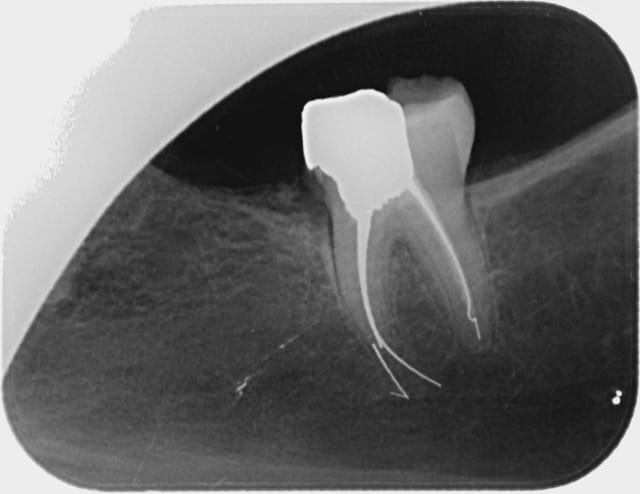

C'est encore une endo à 15 mm de l'apex?

Img 3657 cwjvqm - Eugenol